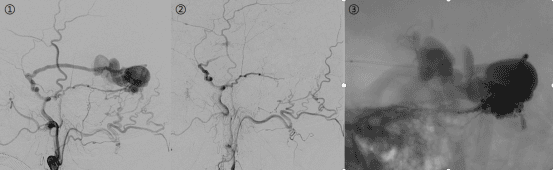

硬脑膜动静脉瘘发病率低,临床表现不典型,可有头痛、耳鸣、视力下降、眼红等症状。图

1 侧窦区硬脑膜动静脉瘘术前,图2瘘口闭合,静脉不显影,图3 供血动脉、瘘口及引流静脉栓塞铸型良好